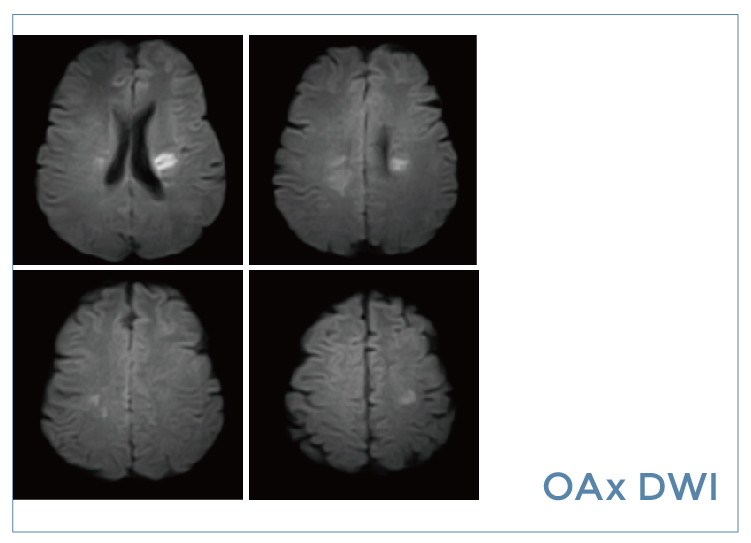

【朗润影像档案】20190823磁共振影像病例结果讨论